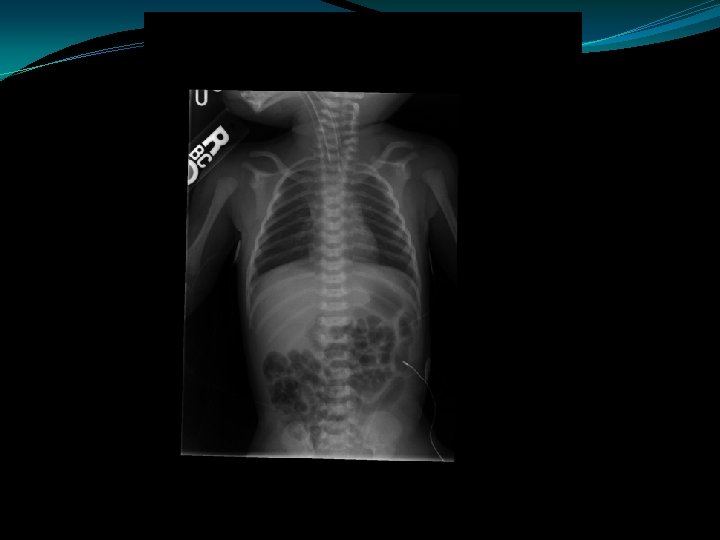

Duodenal Atresia �Polyhydramnios �Partial obstructions: duodenal web, duodenal stenosis, annular pancreas � 40% of cases associated with trisomy 21 �Most common gut atresia in neonates �“Double bubble”

Malrotation/Volvulus Abdominal XRay �Normal film -20% �Dilated duodenal bulb and paucity of distal bowel gas �Double bubble sign �Distal gas filled bowel loops; gas filled volvulus (obstructed mesenteric veins prevent absorption of gas